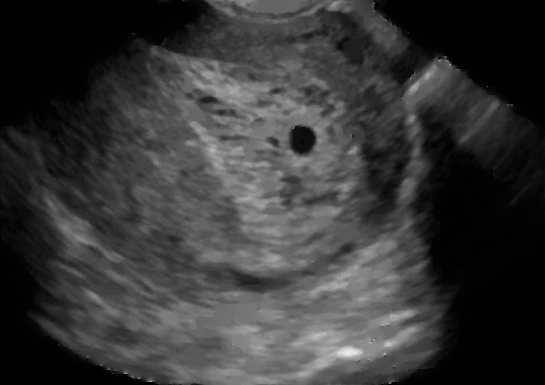

Example 2: restoration of images corrupted by blur and SPN or AWLN. In this example we evaluate the performance of the proposed TV-L1 model on three medical test images lungs (), Fig. 5 (a), ecography (), Fig. 6 (a), and aneurism (), Fig. 7 (a), synthetically corrupted by Gaussian blur of parameters band=5 and sigma=1 and by two types of impulsive noise, namely SPN and AWLN.

| (a) original | (b) TV-L1 (ISNR = 22.13) | (c) zoom of (b) |

![]() |

| (d) corrupted | (e) TVp-L1 (ISNR = 23.15) | (f) zoom of (e) |

| (g) -map () | (h) TV-L1 (ISNR = 25.46) | (i) zoom of (h) |

| (l) -map () | (m) TV-L1 (ISNR = 28.01) | (n) zoom of (m) |

First, for what concerns corruptions by SPN, in Figs. 5, 6, 7 we report for the three considered test images the original and corrupted image together with the estimated -maps in the first column (with the size of the neighborhoods used for the -maps estimation reported in the captions), the restoration results, obtained by the four compared methods, in the second column (with the achieved ISNR values in the captions) and a zoomed detail of the restored images - green- bordered in Figs. 5 (a), 6 (a), 7 (a) - in the last column.

The reported ISNR values as well as the visual inspection of the restored images and of the zoomed details strongly indicate how the proposed space-variant regularizer allows for higher quality restorations. In particular, it is worth remarking how, with respect to the space-variant TV model, the additional degrees of freedom represented by the scale parameters used in our proposal, yield a sufficient additional flexibility for avoiding unwanted spurious effects - see, e.g., spikes in Figs. 5 (i), 6 (i), 7 (i).